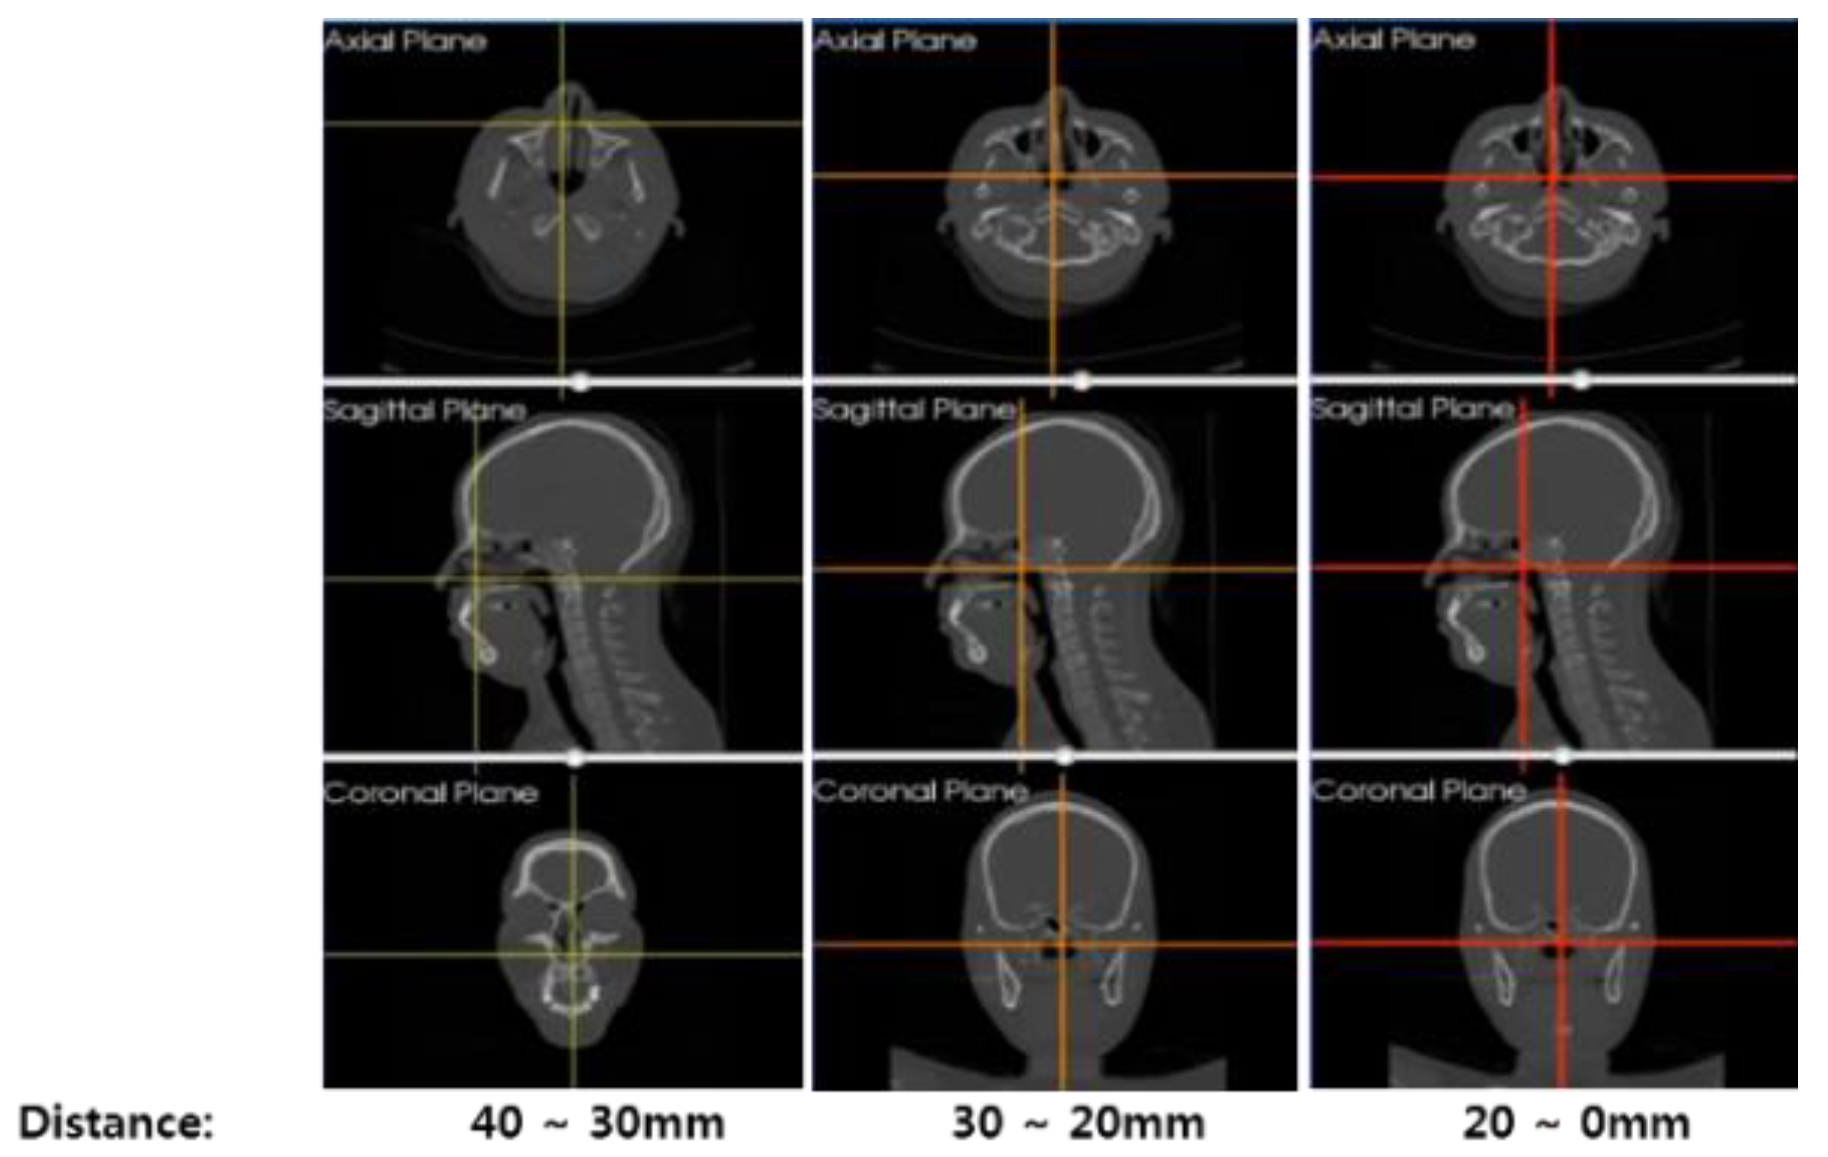

3.2. Registration for Construction of Navigation System